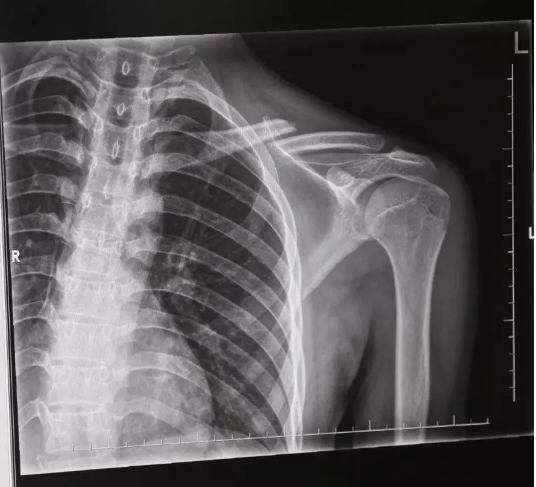

随后,马某某带着年轻男子来到杨庙镇医院检查,经拍X光片,医生诊断这名自称“丁某某”的伤者锁骨骨折,需要手术。见此情形,与“丁某某”同行者以两人无法做主为由,致电一位自称年轻男子亲戚的人。后再与这位亲戚上商量中,其以小伙不是本地人,需要回老家做手术为由,最终让马某某赔偿了一万元。过了一段时间,马某某越想越觉得可疑,3月28日,他拨打110报了警

长丰县公安局刑警大队在接警后,根据马某某的描述,并到达事发地医院进行走访得知,受伤的“丁某某”只拍了一个X光片,没有基本的治疗,直接拿钱走人,且双方还未曾互留联系方式,这点引起了警方的注意。

随后,警方对周边城市所有医院在最近的拍的X光片进行核查,发现3月17日至4月7日间,在寿县、凤台、长丰、肥西的多家医院均有名为“丁某某”的锁骨骨折的X光片子。后经过监控录像辨认,发现“丁某某”均为同一人,且均无治疗情况。据此警方认定这是一个碰瓷团伙,于是成立专案组。

“因为拍片可以看出新伤还是旧伤,所以该团伙每雇一个小伙,就利用愈合前的十天内疯狂作案,等到伤口开始愈合后就换人。”办案民警告诉记者,在这十天的时间内,他们选择市郊或县城附近监控较少地区,疯狂作案。而受雇的小伙,基本都是在广东打工,受到每次4、5万元的高额利润的诱惑选择铤而走险,成为了曾某某、何某某等人诈骗的工具。